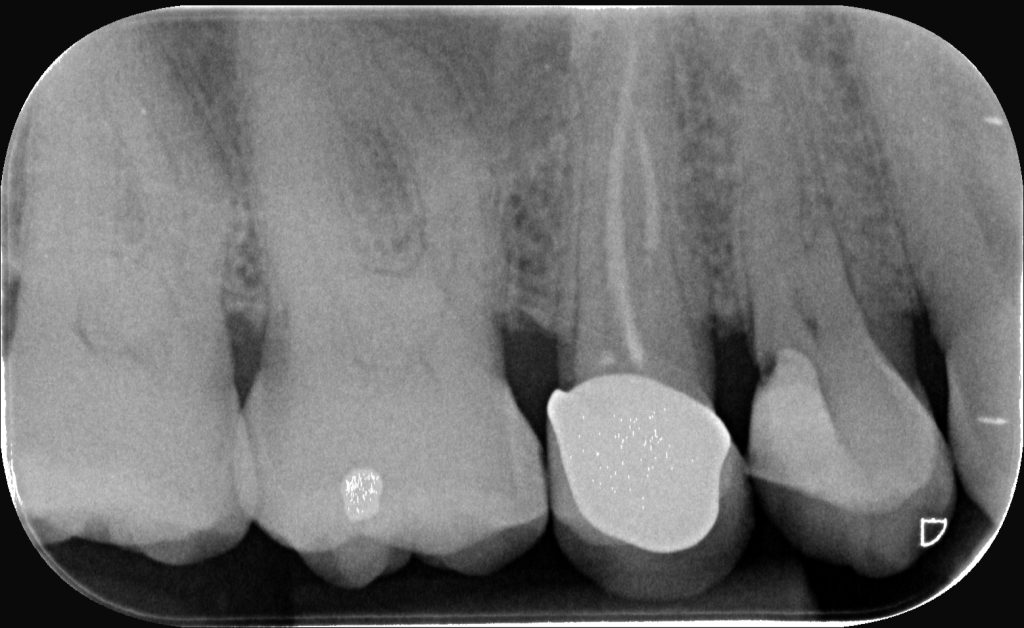

Dans ce contexte, le cas clinique présenté illustre le protocole de pulpotomie tampon à une prémolaire présentant une pulpite irréversible et une hémorragie persistante.